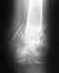

было проведено 4 операции ТБС,но ни одна операция не помогла,боли при ходьбе не уменшились,а наоборот усилились.Операций были проведены первых 2 УНИТО на Московской,3 на пер Банковском.С 4 операцией обратился Курган в клинику имени Элизарова.Что мне делать?

4 операции ТБС

Что за "4 операции ТБС"? В справке, которую дали при выписке, какой написан диагноз, как называется операция?